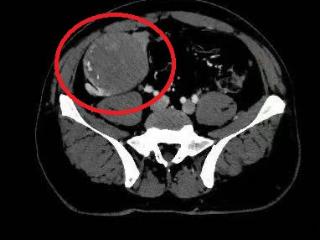

多学科协作攻坚克难 北京大学人民医院青岛医院成功摘除患者腹腔12cm腹膜后肿瘤